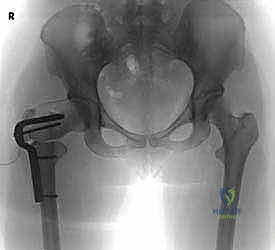

4. التثبيت الداخلي (Internal Fixation)

بعد الوصول إلى الزاوية المطلوبة، يجب تثبيت العظم بقوة لضمان التئامه في الوضع الجديد. يستخدم الأستاذ الدكتور محمد هطيف أحدث الشرائح المعدنية المخصصة (مثل Blade Plates أو Dynamic Hip Screws - DHS) المصنوعة من التيتانيوم عالي الجودة لضمان الثبات المطلق.

بناءً على التخطيط المسبق، يتم إدخال سلك دليلي في عنق ورأس الفخذ تحت توجيه الأشعة السينية المستمرة داخل غرفة العمليات (C-arm Fluoroscopy) لضمان الدقة المتناهية في الزوايا.

3. القطع العظمي (The Osteotomy)

باستخدام مناشير جراحية دقيقة جداً، يتم إزالة وتد عظمي (Wedge) ذو حجم وزاوية محسوبة مسبقاً من منطقة بين المدورين. هذا القطع هو الذي يسمح بإعادة توجيه رأس الفخذ إلى الوضعية الميكانيكية المثالية.